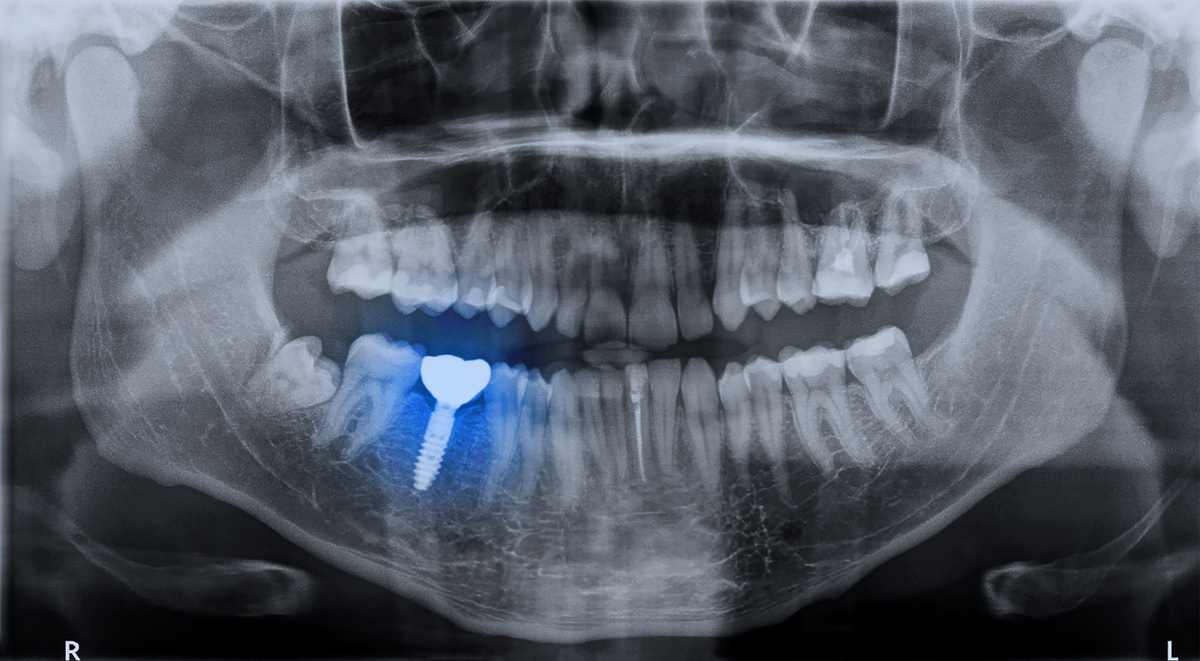

Getting a tooth extraction can leave your smile feeling incomplete, and you may wonder how long you’ll have to wait before restoring your confidence and your smile’s appearance with a dental implant. The answer depends on several factors, including the condition of your jawbone, your overall health, and the type of implant procedure that’s right for you. At Richard Hardt,